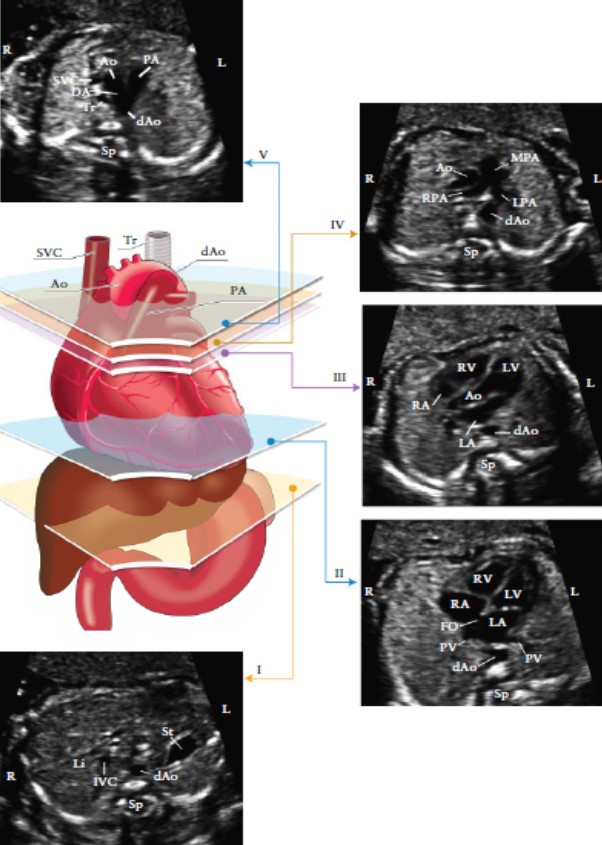

Рисунок 3. Пять поперечных срезов для оптимального сканирования сердца плода. На цветном изображении представлены: трахея (Tr), сердце и магистральные сосуды, печень и желудок, с пятью срезами в серо- шкальном режиме, обозначенными соответствующими многоугольниками.

(I) наиболее каудальный срез, на котором представлены желудок (st), поперечный срез нисходящей аорты (d Ao), позвоночник (Sp), печень (Li). (II) четырехкамерный срез сердца, представленных правым желудочком и левым желудочком(RV, LV) и предсердиями (RA, LA), овальное окно (FO), легочные вены ( PV) справа и слева от dAo. (III) Выходной тракт левого желудочка: ствол аорты (Ao), LV, RV,LA, RA и поперечное сечениеАо. (IV). Немного сместив датчик к головке плода (выходной тракт правого желудочка) выявляется главный ствол легочной артерии (MPA), бифуркация на правую (PPA) и левую (LPA) легочные артерии и поперечное сечение восходящей аорты (Ао) и dAo. (V) трехсосудистый срез и трахея, демонстрирует верхнюю полую вену (SVC), пульмональную артерию (РА), артериальный проток (DA), поперечный срез дуги аорты (от проксимальной Ао к dAo) и трахею (Tr). IVC-нижняя полая вена, L- лево, R- право. Модифицировано с разрешения Yagel et al. [70]

В идеальном случае, все проекции выходных трактов визуализируются относительно легко. Тем не менее, не у всех пациентов при рутинном УЗИ возможна визуализация вышеописанных срезов. Проекции выходного тракта левого и правого желудочков можно получить сдвинув (или наклонив под углом) датчик к головке плода (рисунок 4), начиная с проекции четырех камер сердца и до получения нормального поперечного среза аорты и главной легочной артерии и места их отхождения. Также можно выявить бифуркацию легочной артерии (Приложение S1, Планы 1 и 2).